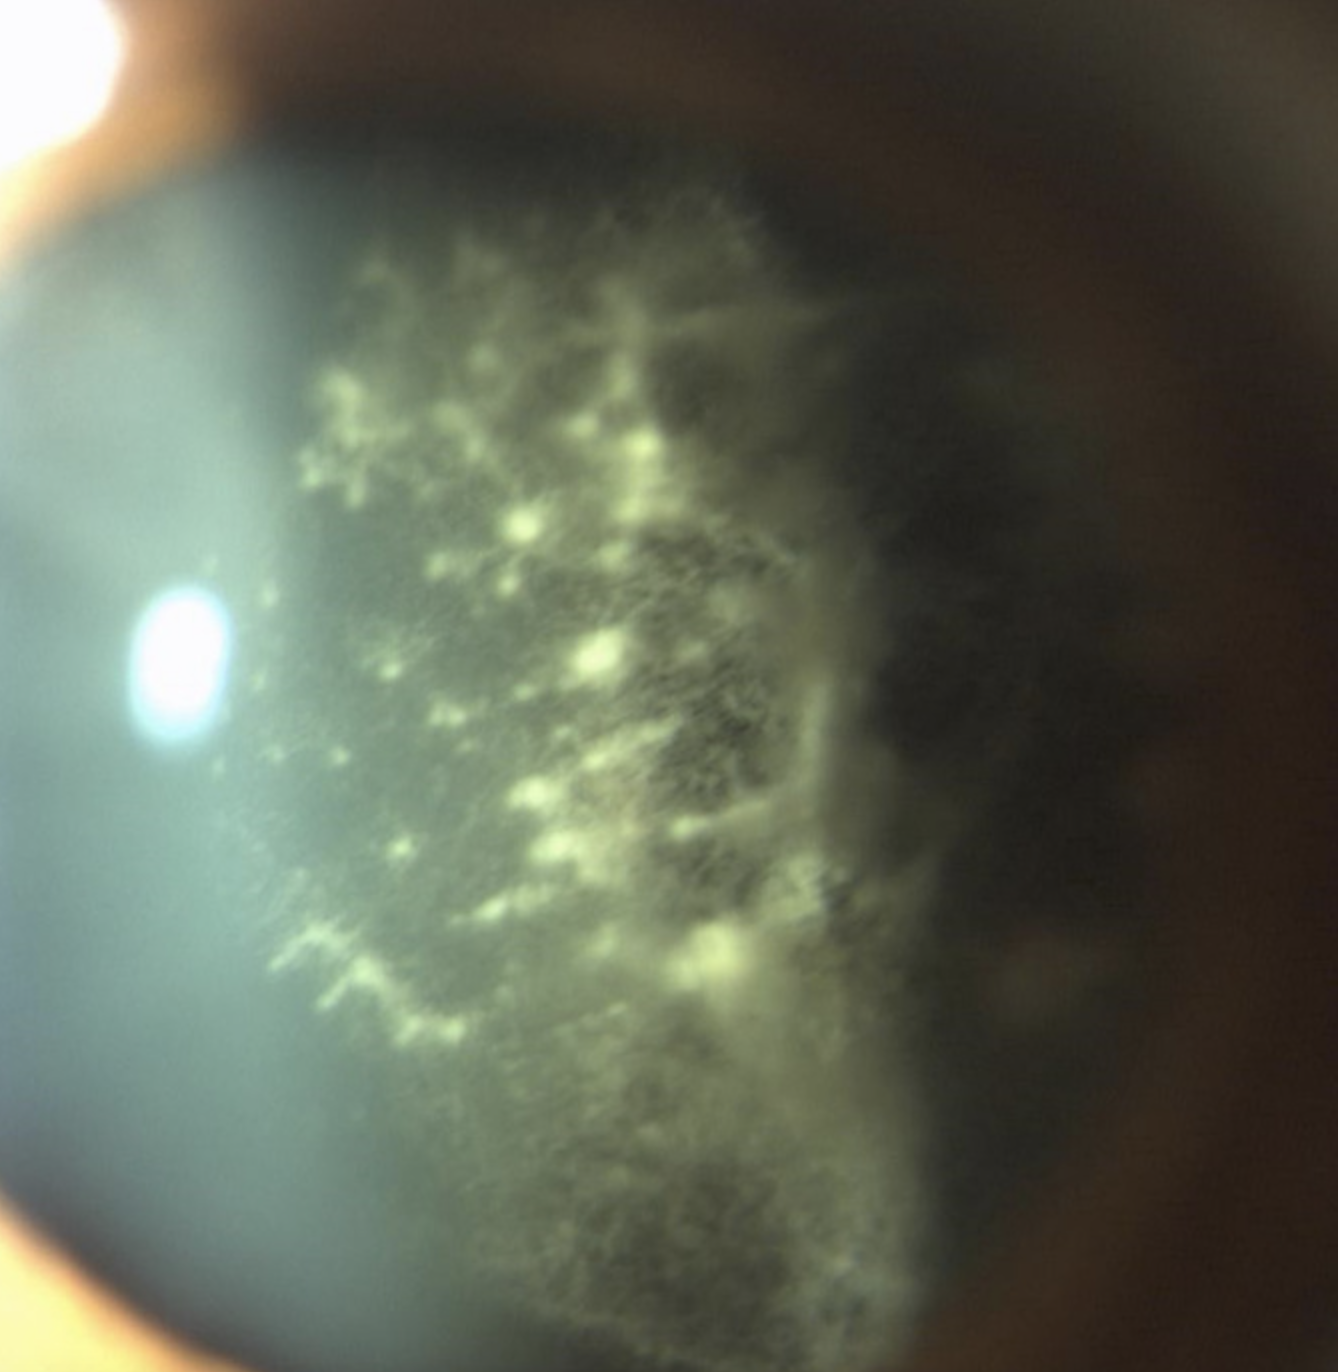

⚠: Retrolentale Glaskörper-Amyloid-Trübungen.

Abbildung 3a: Klassisches Erscheinungsbild von retrolentalen Glaskörper-Amyloid-Trübungen6

In der Spaltlampenuntersuchung von Patienten mit Amyloidose kann sich folgendes pathognomonisches Zeichen zeigen: